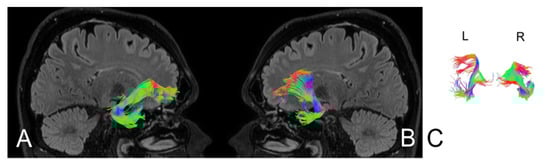

| Parameters | Left side | Right side | Left side | Right side |

| Number of fibres | 160 | 205 | 185 | 208 |

| Volume of tract [mm2] | 1125 | 18440 | 1280 | 18559 |

| Length of tract [mm] | 75.5 | 88.0 | 86.4 | 89.0 |

| FA | 0.715 | 0.885 | 0.785 | 0.880 |